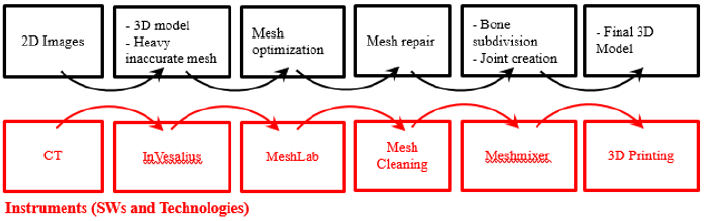

Surgical planning is evolving step by step with the improvement of the technology available for diagnostic imaging. In The early 1900 ‘ the only diagnostic imaging technique used was the radiology. Nowadays there are modern systems of Acquisition as the Computerized tomography (TC) that provide the surgeon with detailed reconstructions of the patient’s anatomy. The proposed methodology wants to take a further step forward, by transferring the planning from the virtual to the physical world thanks to the printing of three-dimensional anatomic parts. The Workflow To get to the printing of anatomic models start from Tomographic image acquisition through the traditional non-invasive acquisition technique, the TC. Then, a series of software are needed to convert these images in a CAD-readable file format for the 3D printing software [1].

As mentioned in the previous paragraph, the images extrapolated from the CT are not always sufficiently clear to allow the surgeon to elaborate in detail the procedure to be performed before the operation. Accordingly, to the new workflow, a 3d model from CT scan should be produced. This model may be used to during the study phases of the operation and/or during the surgical operation itself. The primary goal that to achieve thanks to the three-dimensional anatomical reproduction is the reduction of the duration of the surgical procedure, with consequent reduction of anesthesiologic times and surgical wounds. Moreover, the reduction of fluoroscope in the operating room should occurs. The process can be subdivided in six consecutive steps (Figure 6).

From CT to 3D

The methodology proposed in this paper uses tomographic images as a starting point for generate a three-dimensional model. Thanks to this technique, the density of tissues crossed by X-rays is converted into different gray levels. The program in Vesalius was chosen for this purpose as in it is a free medical software. It is able to generate virtual reconstructions of structures of human body based on CT scans. The first operation to be performed in in Vesalius is importing a DICOM format file (Figure 7)[8].

Following the import, the software allows to visualize the biological structure of interest in the three main axes of the human body (Figure 8)[10]. The next step is to segment the image using a colored mask. The mask is nothing but gray threshold level comparable to a certain tissue density. By setting the density range, the software highlights a specific region and creates its three-dimensional model, eliminating the rest. There is the possibility of pre-defined range (for example: compact bone, spongy bone, skin, muscular tissue etc.) or it can be changed manually. After the correct identification of the mask, the 3D surface is generated using the proper command (Figure 9). In the analyzed case it was preferred to use the “ Compact bone (adult) “ because the range was more limited avoiding other possible tissue inclusion. When the mask covers the right areas, the creation of the three-dimensional surface is performed. This is displayed in the lower right window (Figure 10). Once the 3D surface is created and exported in STL format for further modifications. Generally, the mesh created by In Vesalius is coarse and not homogeneous, so it needs an optimization process.

The Optimization Process